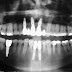

Radiografia Panorâmica

A radiografia panorâmica é uma técnica peculiar que possibilita a relação rara de estruturas anatômicas não vista em qualquer outra radiografia. Ela não pode ser definida em um único conceito, por isso, na literatura, para explicá-la há necessidade de definir sete conceitos. O primeiro é que as estruturas apresentam-se aplainadas e espalhadas, isso é possível entender quando se observa uma radiografia panorâmica, em que por exemplo o assolho da fossa se estende horizontalmente na radiografia. Fato possível porque temos o registro plano de uma estrutura curva.

Outro conceito é que a radiografia panorâmica mostra dois tipos de imagem real: real única e real duplicada. Quando o feixe de raio x intercepta a estrutura anatômica apenas uma vez evidenciamos a imagem real única, mas quando intercepta a estrutura anatômica duas vezes há o registro de imagem real duplicada. Exemplo disso é a coluna vertebral, palato duro e mole e quando existe tórus palatino. Podemos explicar as imagens fantasmas também através de um conceito, em que se apresenta maior que a imagem real, principalmnete no sentido vertical.

Na radiografia panorâmica também mostra os espaços aéreos, formados por ar, que não atenuam os feixes de raio x mostrando-se radiolúcidos. Este exame registra também tecidos moles como gengiva. E isso é uma vantagem, visto que mostra uma visão realmente ampla.

Todos estes conceitos explicam as peculiaridades da radiografia panorâmica, mas o que deve ser realmente ressaltando é o fato de podermos ver em uma única radiografia várias estruturas anatômicas adjacentes associadas de forma rara. Isso facilita muito a elaboração do plano de tratamento para o implantodontista.